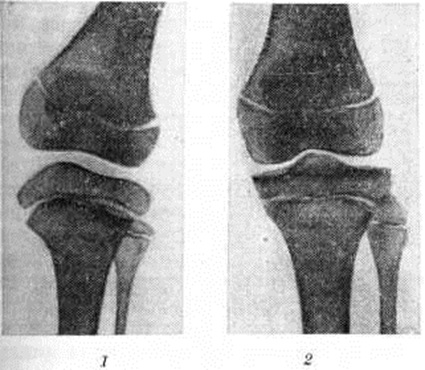

Рис. 2.

Рентгенограммы коленных суставов: 1 — при болезни Моркио, видно уплощение, расширение эпифизов и уменьшение их высоты; 2 — в норме (дано для сравнения).

При рентгенологическое исследовании длинных и коротких трубчатых костей наблюдается нарушение роста эпифизов костей, проявляющееся в их уплощении, расширении и уменьшении высоты (рисунок 2) при отсутствии существенного торможения роста в эпифизарных хрящах. При рентгенографии позвоночника, как правило, обнаруживается заметное уплощение и расширение тел позвонков от CII до Lv — платибрахиспондилия (рисунок 3), чем и объясняется характерное укорочение туловища и необычно короткая шея при Моркио болезнь; межпозвоночные диски при этом мало изменены или не изменены вовсе. Переднезадний размер грудной клетки увеличен, межрёберные промежутки сужены, грудина дугообразно деформирована. Все эти изменения выявляются при обзорной (желательно телевизионной) рентгеноскопии с последующей обязательной рентгенографией тех отделов скелета, в которых обнаруживаются наиболее выраженные изменения.